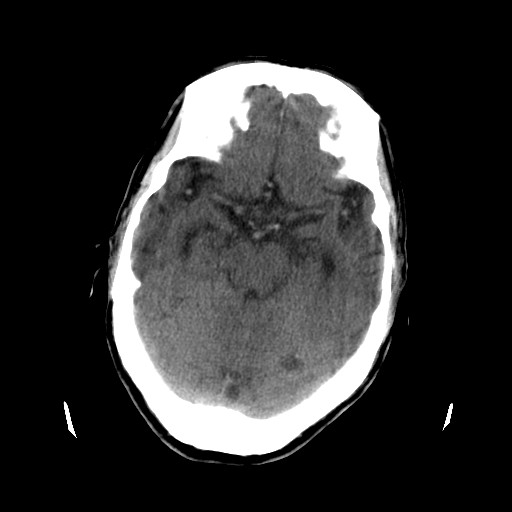

患者,男,70岁,清晨(10小时前)无法自行起床,家人无法唤醒,现昏迷,大小便失禁

左颞枕叶交界区可见类圆形高密度区,边缘可见环形更高密度影,并夹杂有点状钙化影,占位效应明显,未见明显水肿影,考虑脑膜瘤出血

左颞枕叶交界区可见类圆形高密度区,边缘可见环形更高密度影,侧脑室后角明显受压而周围未见明显水肿.考虑脑膜瘤伴出血可能性大不排外血管畸形.建议mr进一步检查.

左颞枕叶交界区的类圆形高密度区首先考虑脑膜瘤卒中,病人左侧小脑半球的还有多个囊性低密度,要考虑同时伴有梗塞的可能。

这个病人做ct时已经10小小时了,按说出血多稳定了,这么少的出血和这么小、少的梗塞怎么会导致病人昏迷?而脑干、脑桥和中脑都没有发现出血或梗塞,也没有明显的颅内高压,真的很奇怪。